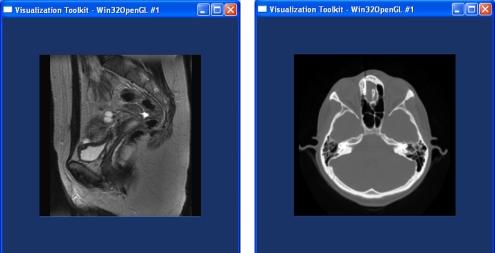

利用开源库实现医学成像工具的快速发展。

Rapid development of medical imaging tools with open-source libraries.

Rapid prototyping is an important element in researching new imaging analysis techniques and developing custom medical applications. In the last ten years, the open source community and the number of open source libraries and freely available frameworks for biomedical research have grown significantly. What they offer are now considered standards in medical image analysis, computer-aided diagnosis, and medical visualization. A cursory review of the peer-reviewed literature in imaging informatics (indeed, in almost any information technology-dependent scientific discipline) indicates the current reliance on open source libraries to accelerate development and validation of processes and techniques. In this survey paper, we review and compare a few of the most successful open source libraries and frameworks for medical application development. Our dual intentions are to provide evidence that these approaches already constitute a vital and essential part of medical image analysis, diagnosis, and visualization and to motivate the reader to use open source libraries and software for rapid prototyping of medical applications and tools.

快速成型是研究新的成像分析技术和开发定制医疗应用的重要元素。在过去十年中,开源社区以及用于生物医学研究的开源库和免费可用框架的数量显著增长。它们所提供的内容如今被视为医学图像分析、计算机辅助诊断和医学可视化的标准。对成像信息学领域(实际上,几乎在任何依赖信息技术的科学学科中)经过同行评审的文献进行粗略回顾表明,当前依赖开源库来加速流程和技术的开发与验证。在这篇综述论文中,我们回顾并比较了一些用于医疗应用开发的最成功的开源库和框架。我们的双重目的是提供证据证明这些方法已经构成医学图像分析、诊断和可视化的重要且必不可少的部分,并激励读者使用开源库和软件进行医疗应用和工具的快速成型。